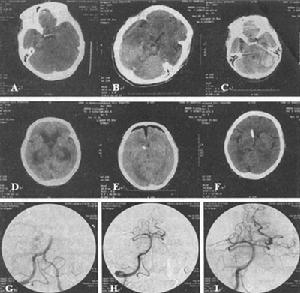

5.頭顱CT 掃描(CT) 臨床表現為腔隙性腦梗死的患者,CT 見有腔隙性梗死灶者占66%~76%。CT 對幕上>5mm 的腔隙病灶易於發現,而對<5mm 或位於腦幹的病灶常難以檢出。Rascal 等報導單純運動性輕偏癱綜合徵者,病後36h 檢查陽性率高達97%。一般病後10 天左右更易出現陽性改變。

(1)非增強掃描:病灶主要位於基底節區、丘腦、內囊、腦幹或放射冠、側腦室旁,呈圓形或橢圓形低密度灶,邊界清楚、直徑2~20mm,占位效應輕,一般僅為相鄰腦室受壓,多無中線結構移位。梗死區密度約於4 周后接近腦脊液密度,並呈現萎縮性改變,即同側側腦室和(或)鄰近腦池、腦溝局限性擴大,中線結構可有輕度的同側移位。

(2)增強掃描:梗死後3 天~1 個月,病灶可呈均勻或斑片狀強化,以2~3周時此效應最為明顯。待病灶密度與腦脊液密度相等時則不再強化。

(3)多發性梗死痴呆的CT 掃描徵象:①腦皮質或皮質下多發的大小不一的低密度梗死灶,主要分布於基底節區及額、顳、枕葉皮質區。②大部分病例可呈腦萎縮改變,即腦室或腦溝擴大,腦皮質、髓質萎縮。③可伴有Binswanger 病(皮質下動脈硬化性白質腦病,SAE)CT 影像特徵:腦室周圍及半卵圓中心白質內的大致對稱性低密度影,呈月暈狀或傘狀,邊緣模糊,多位於側腦室前方或後方。灰/白質密度比值增加。

6.磁共振(MRI) MRI 對腔隙性腦梗死的檢出率明顯優於頭顱CT 掃描,尤其對腦幹及小腦內的腔梗病灶。病後72h,75%患者的MRI 可顯示≤15mm 的腔隙性病灶,5 天內其檢出陽性率可達92%。急性期腔梗病灶在MRI 的影像特點為T1信號減低、T2 信號增高,其中以T2 信號增高改變更為敏感。